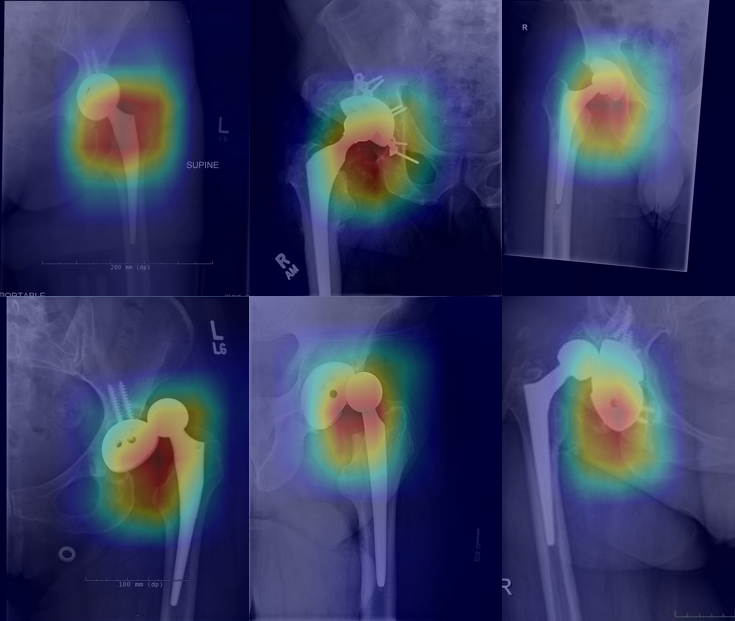

Selected research and applied deep learning.